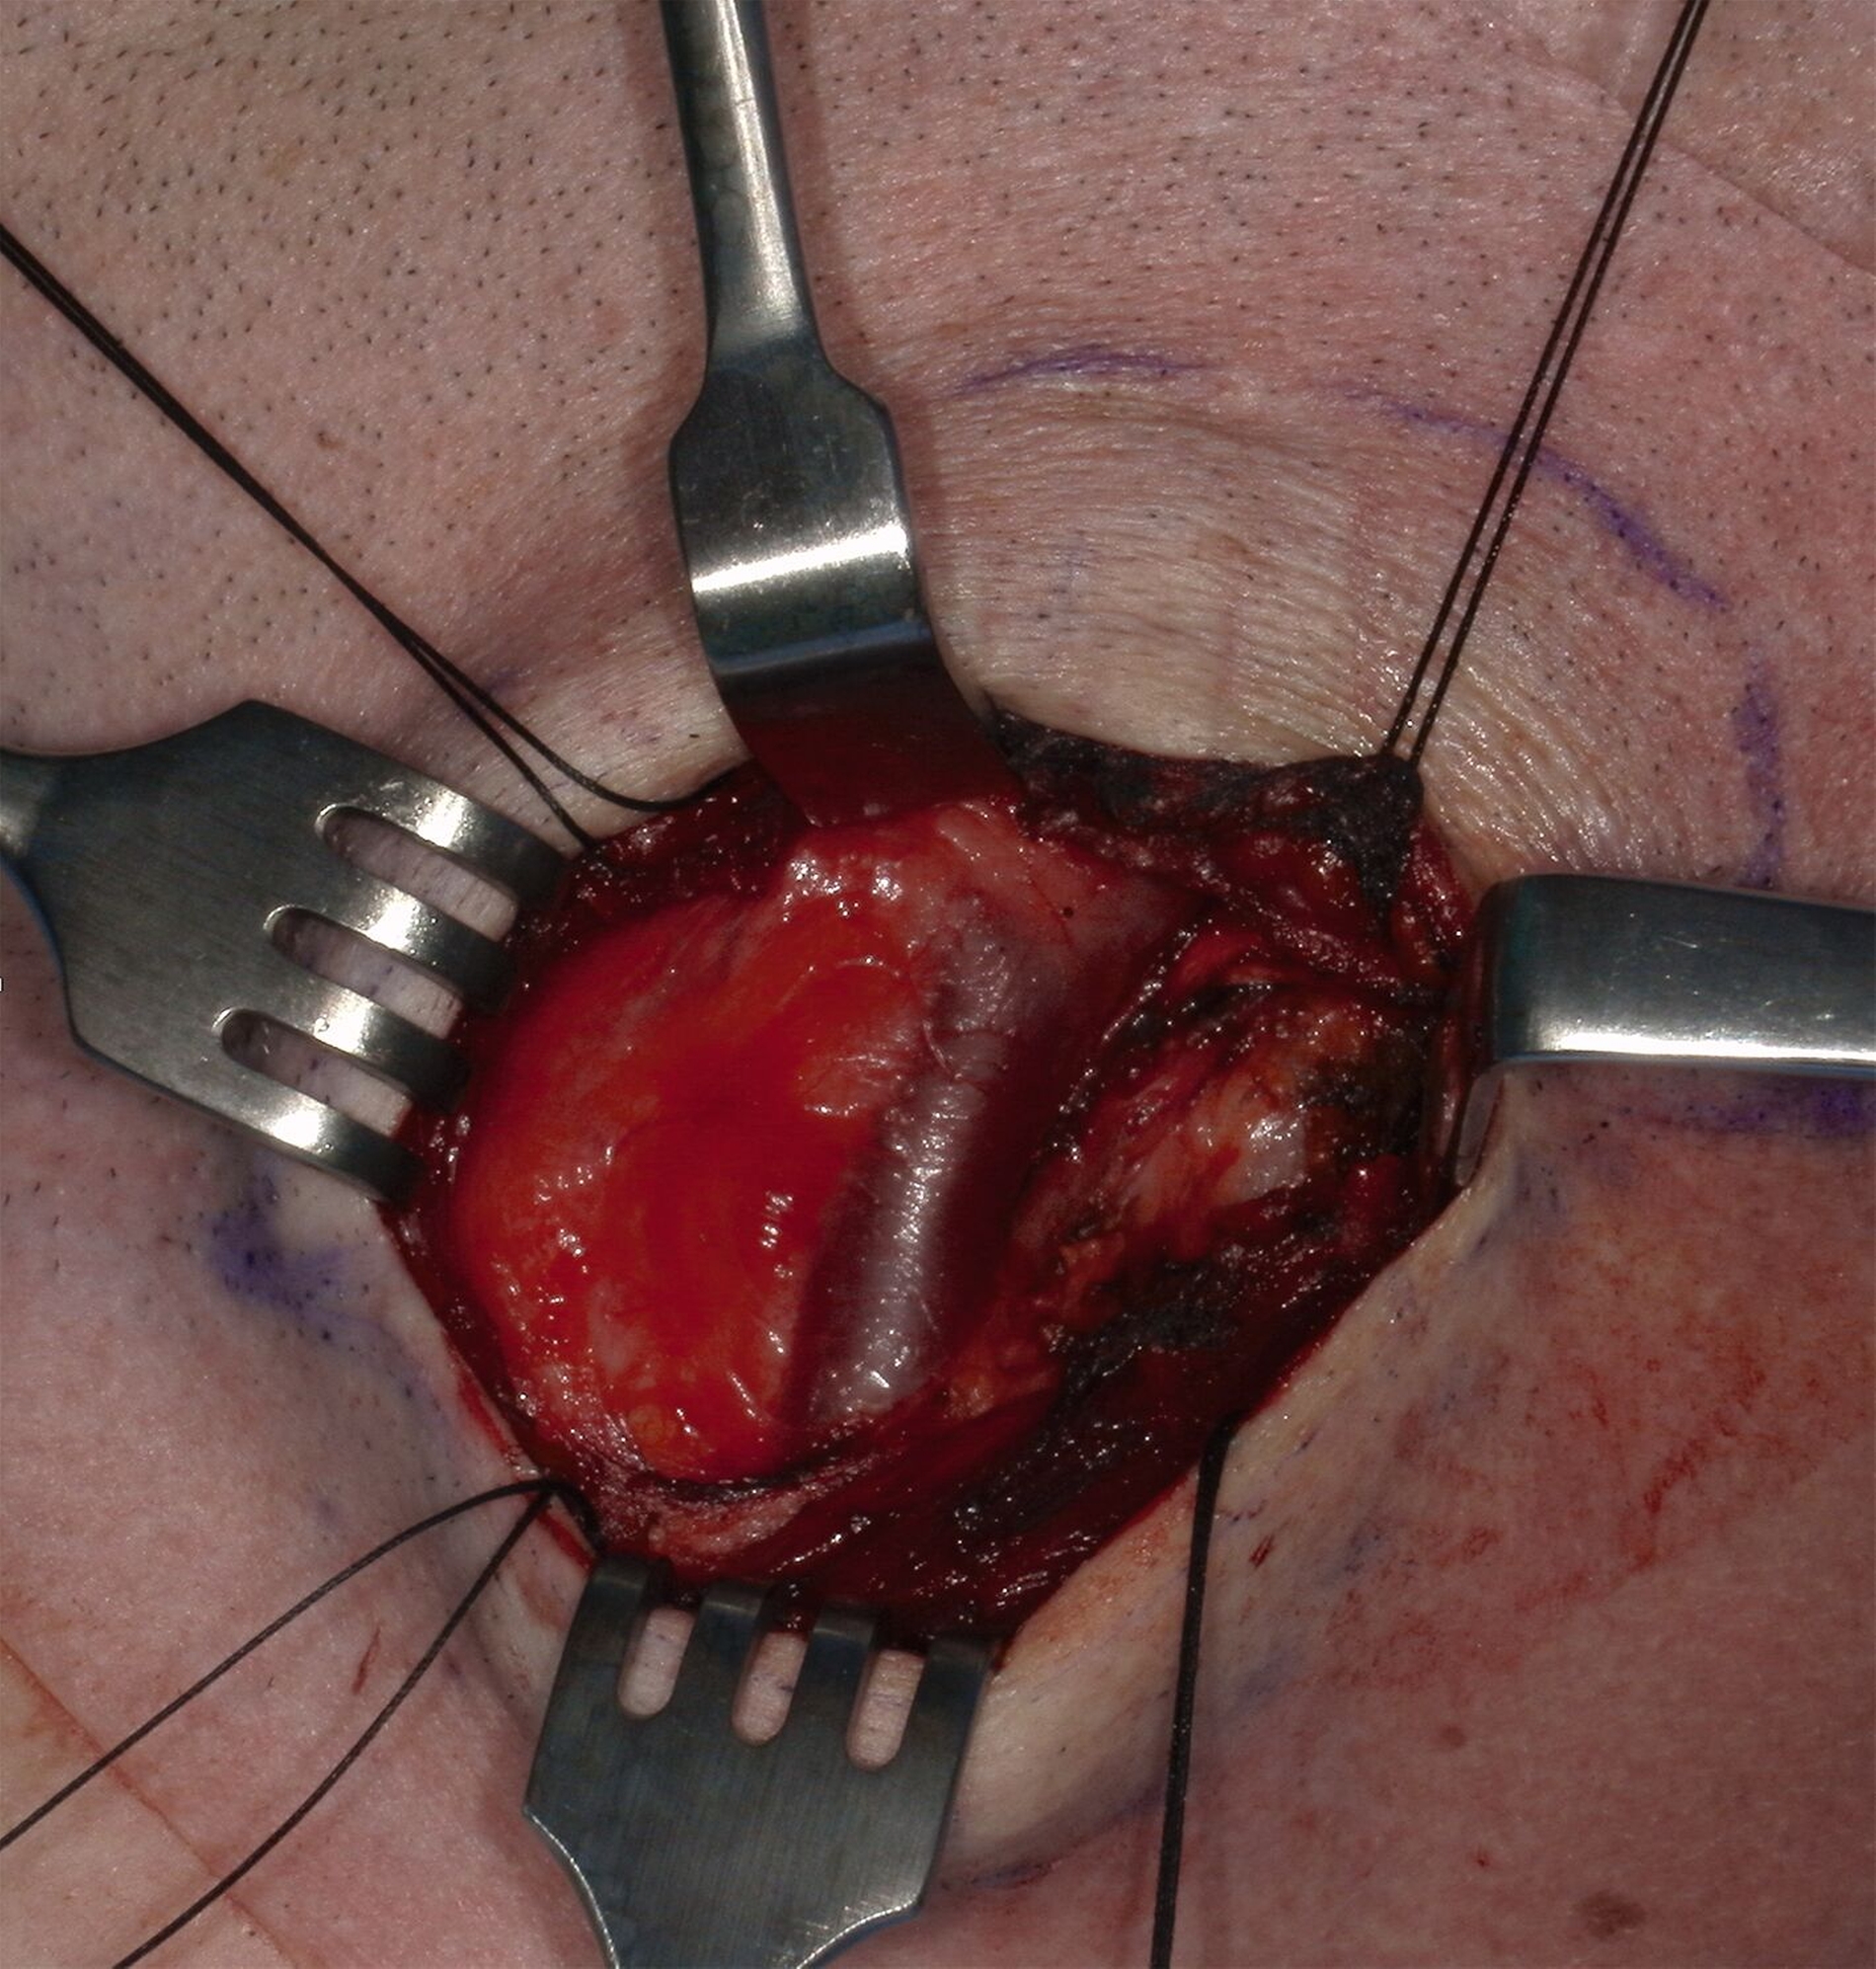

In Zusammenschau der Befunde und aufgrund einer deutlichen Größenprogredienz verständigten wir uns im Konsens mit dem Patienten auf eine Entfernung des Befunds. Die Operation erfolgte einige Wochen später in Intubationsnarkose. Dabei wurde über einen submandibulären Zugang der Befund zunächst unter Schonung der umgebenden Strukturen dargestellt. Bei Exploration des Situs zeigte sich die Raumforderung gut abgrenzbar in der linken Regio cervicalis anterior mit einer bindegewebigen Kapsel überzogen (Abbildung 5). Unmittelbar kaudal des Befunds konnten die großen Halsgefäße identifiziert werden (Abbildung 6).